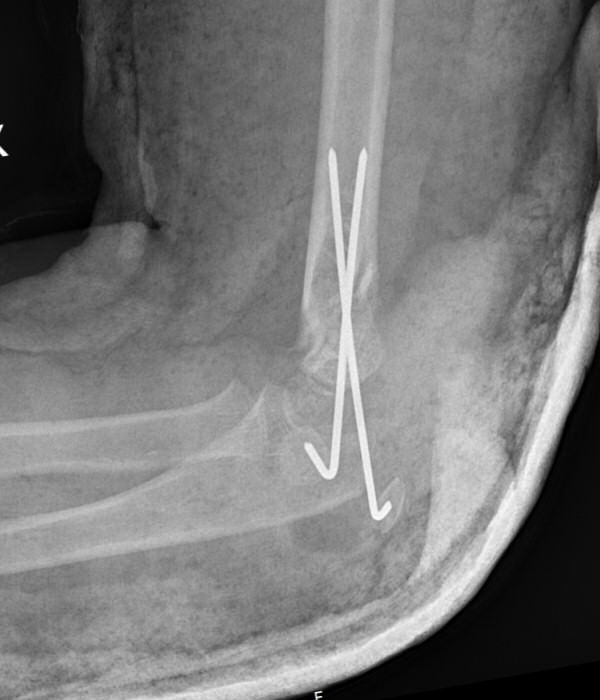

Suprakondylar humerusfraktur, Gartland 3, före och efter operation med stiftning